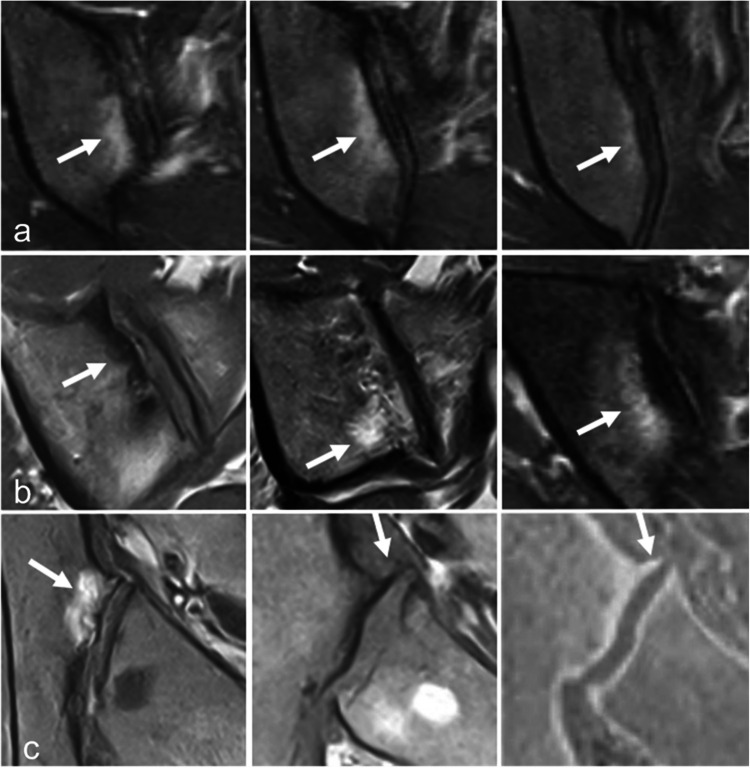

Magnetic resonance imaging of the sacroiliac joints (SIJ) is now frequently performed to detect subchondral inflammatory and structural changes in patients with early axial spondyloarthritis (SpA). However, similar changes can also occur in various other conditions, which may lead to the overdiagnosis of axial SpA. The aim of this article is to review the key imaging features of the most common disorders that may mimic inflammatory sacroiliitis, including mechanical changes and osteoarthritis, osteitis condensans ilii and pregnancy-related changes, other strain related changes, anatomical variants, pediatric SIJs, hyperostosis, infectious sacroiliitis, SAPHO syndrome, hyperparathyroidism, and sacral stress fractures.